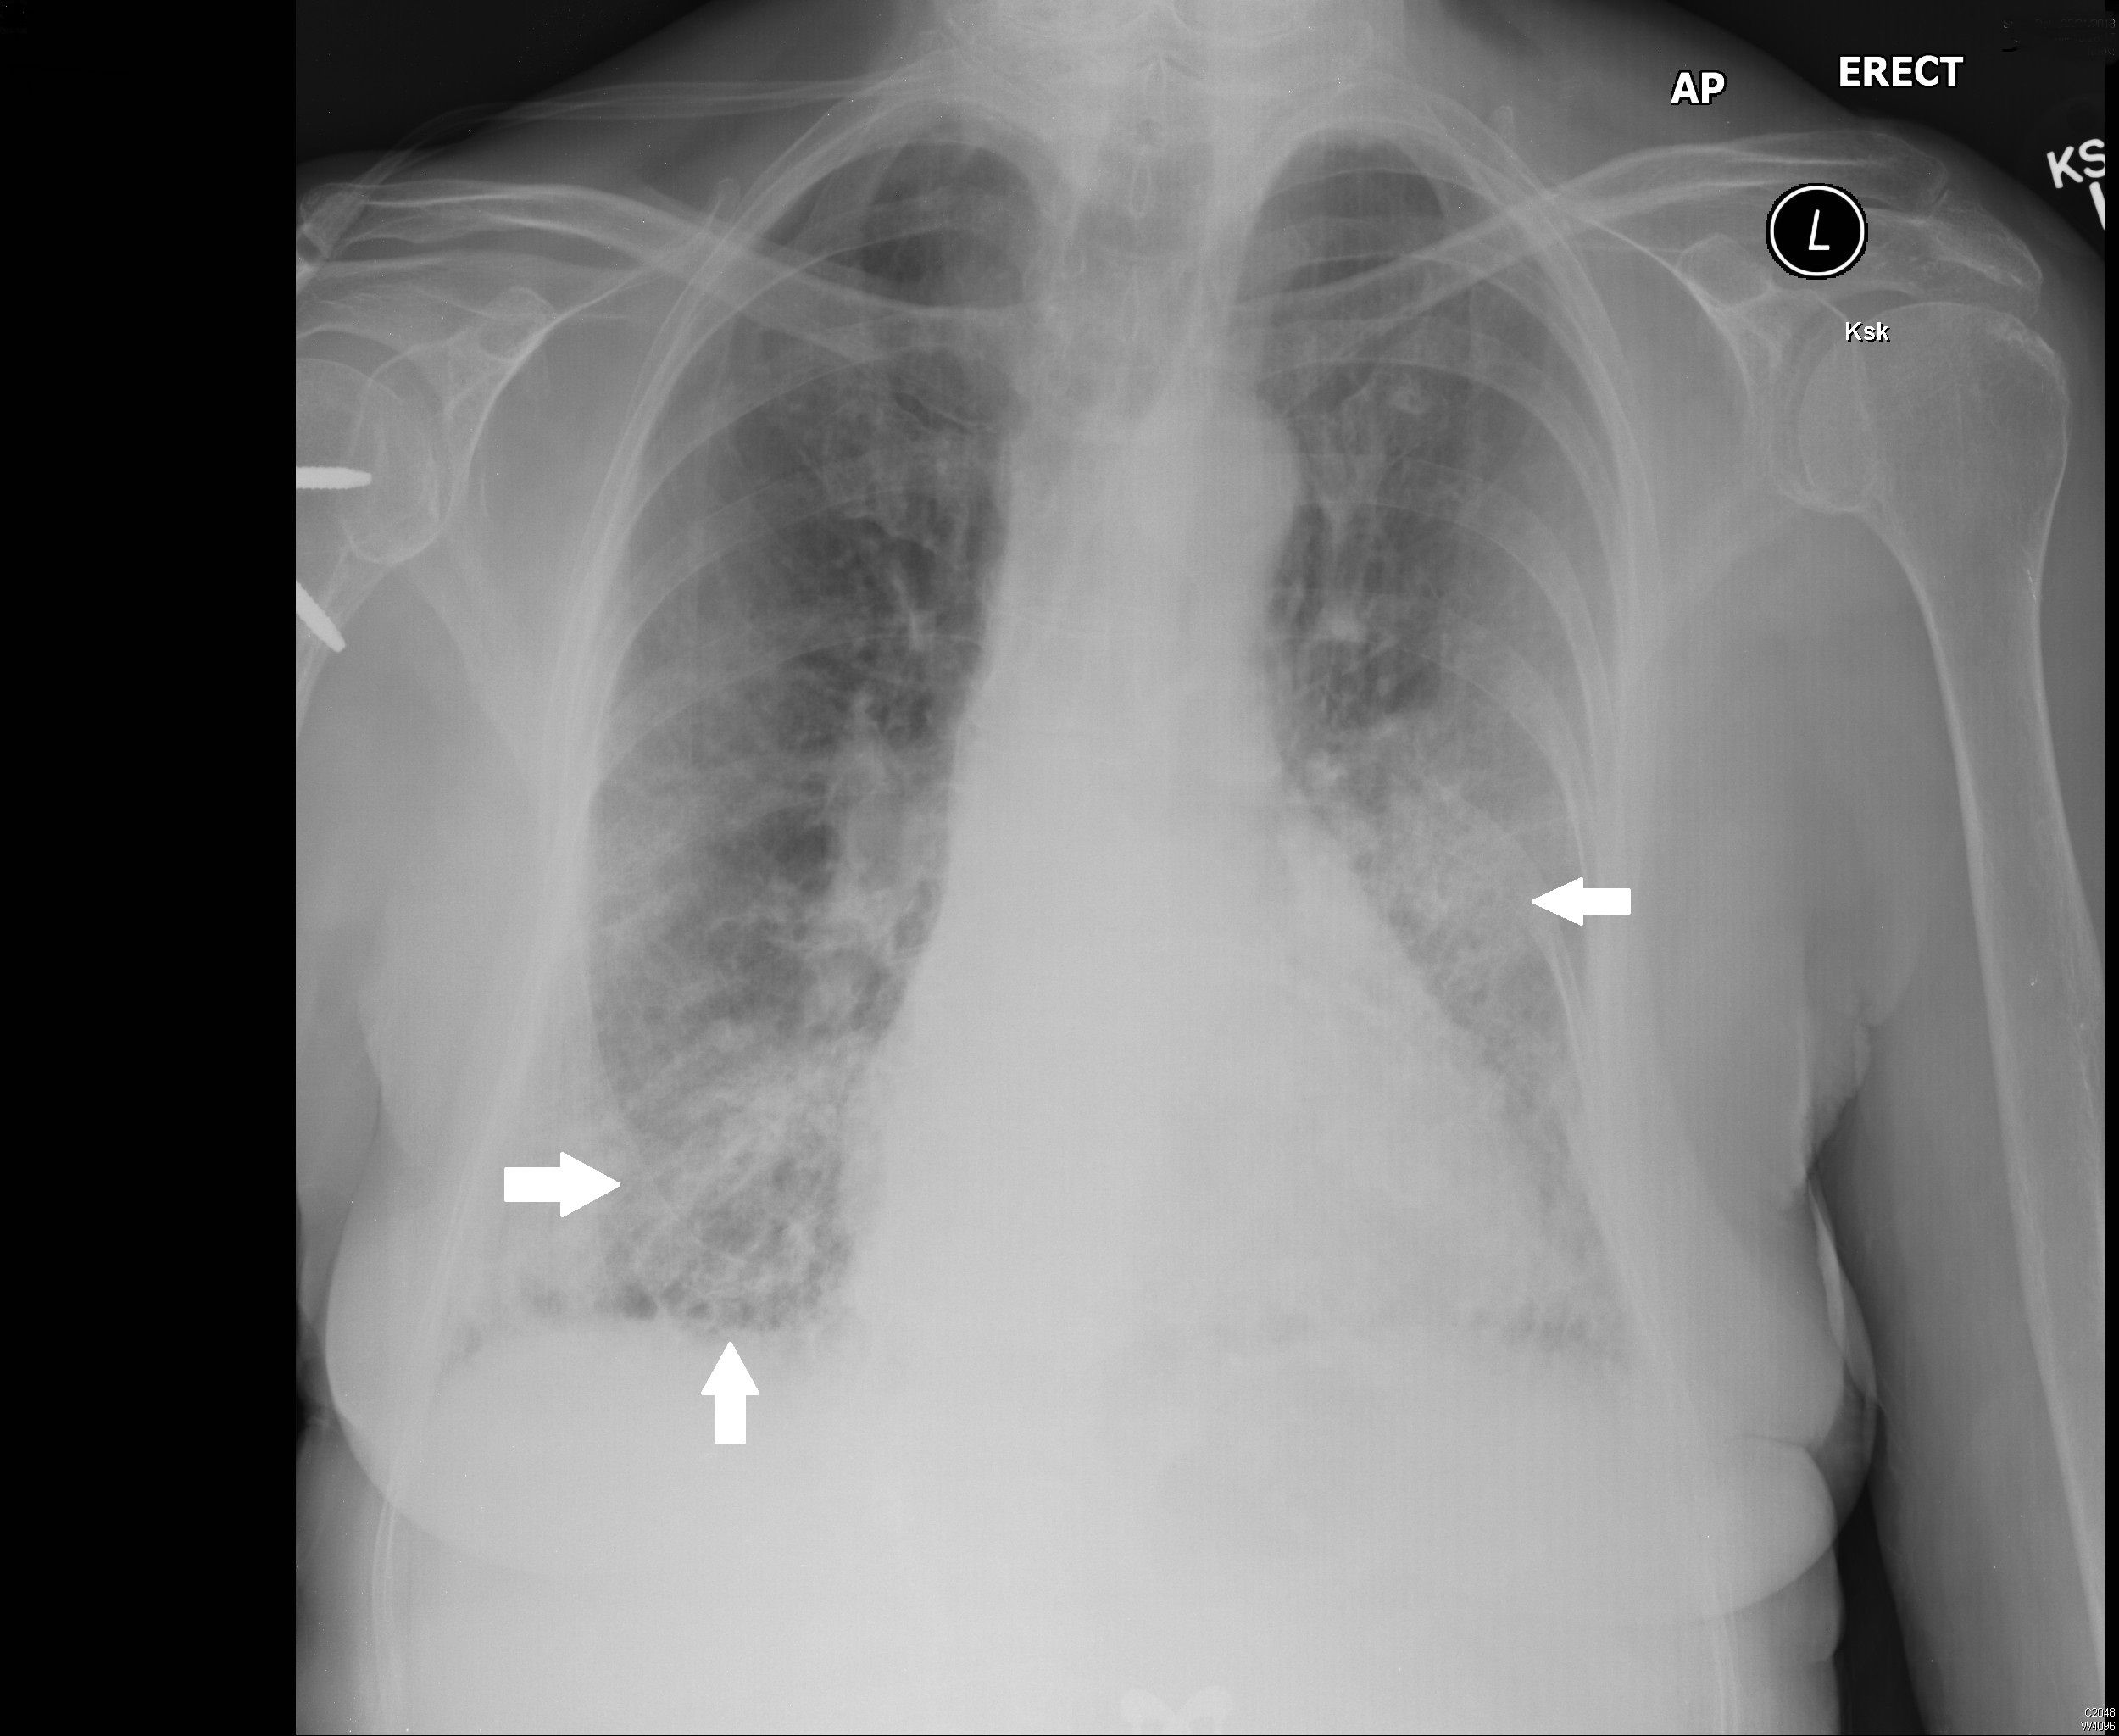

Rheumatoid arthritis (RA)–associated interstitial lung disease (RA-ILD) is an increasingly common extra-articular cause of mortality and morbidity in RA. Here, we present the case of an 82-year-old female suffering from RA-ILD. She presented with a 20-year history of RA with new-onset progressively worsening dyspnoea, pyrexia, and dry cough, which were not responsive to initial antibiotics. Moreover, she had been on long-term methotrexate, which can cause pulmonary disease. Investigations revealed raised inflammatory markers, restrictive lung patterns, and radiological features of ILD. She was treated with a tapering course of oral prednisolone and home oxygen, which provided some symptomatic improvement. Diagnosis of RA-ILD can be challenging due to several contributing factors. Optimal treatment is controversial, and corticosteroids have been widely used but with limited effects. There is evidence directed at potential therapeutic benefit from a number of newer agents, which are discussed.

Tanaka N, Kim JS, Newell JD, Brown KK, Cool CD, Meehan R, et al. Rheumatoid arthritis-related lung diseases: CT findings. Radiology. 2004 Jul;232(1):81-91. DOI: 10.1148/radiol.2321030174.

Akira M, Sakatani M, Hara H. Thin-section CT findings in rheumatoid arthritis associated lung disease: CT patterns and their courses. J Comput Assist Tomogr. 1999 Nov-Dec;23(6):941-8. DOI: 10.1097/00004728-199911000-00021.